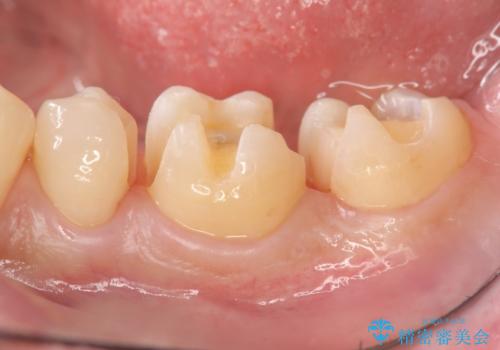

保険適応の白い詰め物レジンインレー下に再発した大きな虫歯治療

- 以前治療した歯の違和感、しみる感じの改善を求めて来院されました。

保険適応の素材、レジン素材による修復が行われていますが、X線写真より修復物の下には透過像(黒い影)が認められ、症状からも虫歯の再発が強く疑われます。